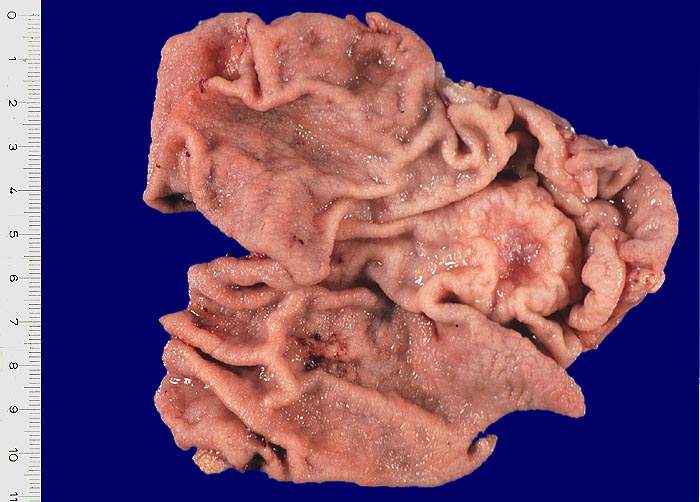

PathoPic – image database / PathoPic ID 3373 - exulzeriertes Magenfrühkarzinom

exulzeriertes Magenfrühkarzinom

maligner Tumor

Magen

Ulzerierter Tumor mit erhabenem Randwall.

Makroskopie